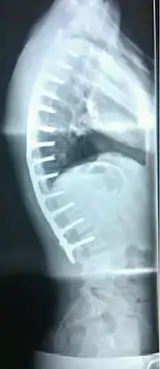

| extreme case of Scheuermann's disease | |

Scheuermann's disease is a bone disease that mainly affects teenage boys, causing their back to abnormally curve.[2]

Scheuermann's disease is considered to be a form of juvenile osteochondrosis of the spine. It is found mostly in teenagers and presents a significantly worse deformity than postural kyphosis. Patients suffering with Scheuermann’s kyphosis cannot consciously correct their posture. The apex of their curve, located in the thoracic vertebrae, is quite rigid.

In addition to the pain associated with Scheuermann's disease, many sufferers of the disorder have loss of vertebral height, and depending on where the apex of the curve is, may have a visual 'hunchback' or 'roundback'. It has been reported that curves in the lower thoracic region cause more pain, whereas curves in the upper region present a more visual deformity. Nevertheless, it is typically pain or cosmetic reasons that prompt sufferers to seek help for their condition. In studies, kyphosis is better characterized for the thoracic spine than for the lumbar spine.[5][6]

The seventh and tenth thoracic vertebrae are most commonly affected. It causes backache and spinal curvature. In very serious cases it may cause internal problems and spinal cord damage, but these cases are extremely rare. The curvature of the back decreases height, thus putting pressure on internal organs, wearing them out more quickly than the natural aging process; surgical procedures are almost always recommended in this case.